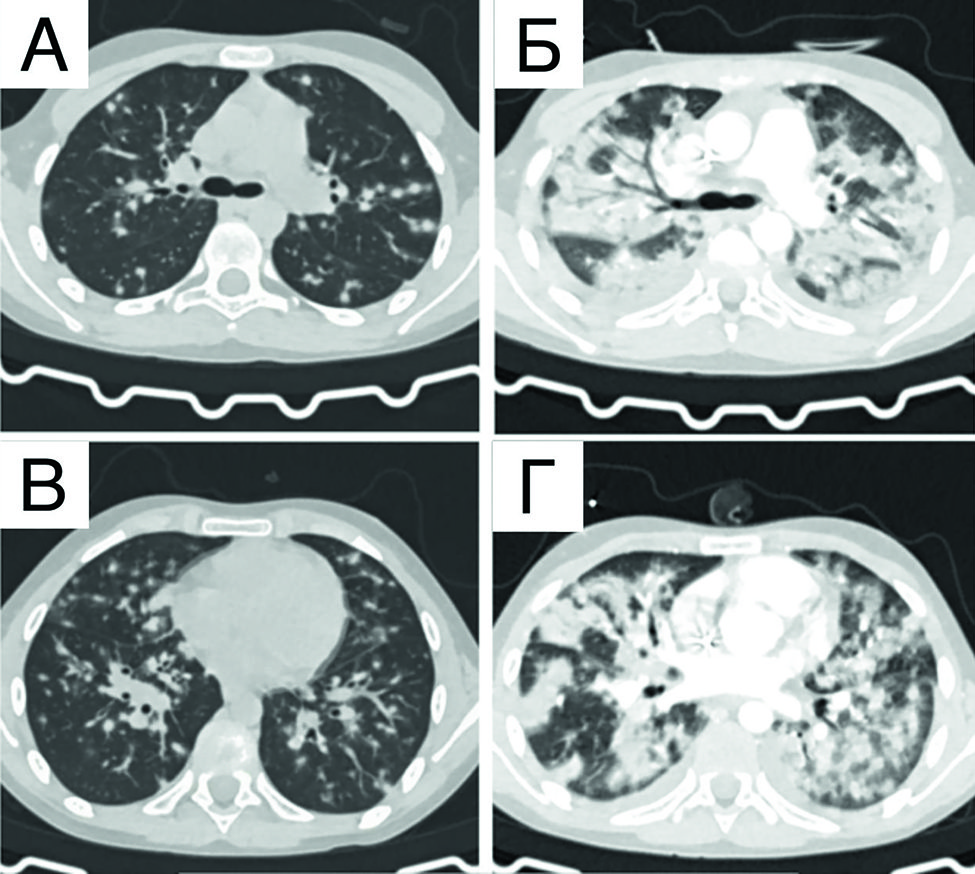

По данным контрольного обследования в объеме КТ органов грудной клетки и органов брюшной полости с контрастным усилением после 4-го и 8-го курсов терапии отмечается выраженная положительная динамика в виде уменьшения патологической специфической инфильтрации обоих легких с уменьшением площади поражения (рисунок 4).

Рисунок 4. КТ органов грудной клетки с контрастным усилением (аксиальная проекция) в динамике на фоне проводимой специфической терапии: А, Г - инициальное поражение; Б, Д - после 4 курсов терапии; В, Е - после 8 курсов терапии

Figure 4. Axial contrast-enhanced chest CT scans showing changes during specific therapy: А, Г - the initial lesions; Б, Д - after 4 cycles of treatment; В, Е - after 8 cycles of treatment